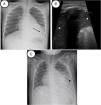

An 8-year-old girl with SCD was admitted to the emergency department due respiratory failure and fever with a pathologic CXR in which left lower lobe infiltration was observed. Due to ACS suspicion, patient was transferred to the PICU for early respiratory support. On admission, LUS showed left lung global collapse with 0.3cm pleural effusion. Both images can be compared in Fig. 2. NIV was initiated to optimize respiratory support, requiring CPAP up to 8cmH2O and FiO2 up to 50%. Clinical and ultrasonographic evolution was favorable, allowing the suspension of support in the following 48h. CXR image after VNI lung recruitment can be compared in Fig. 2.

Patient 2. (A) Initial chest radiography before lung recruitment. Coalescent opacities in left lower lobe (black arrow). No pleural effusion observed. (B) Lung ultrasound image before VNI lung recruitment. Tissular pattern suggesting consolidation (white star). No air bronchogram is observed. The lung partner is similar to the spleen pattern (white point). White arrow shows the doble-rail image of the diaphragm. (C) Chest-X radiography after recruitment. Area of hazy with increased lung opacity (black star).